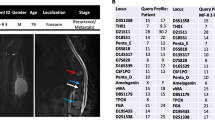

USZ20-EMC1: A 54-year-old female patient initially presented in 2009 with a mass in her knee para-patellar medial right and was diagnosed with an extraskeletal myxoid chondrosarcoma (EMC). After several resections from loco-regional recurrences, the patient underwent an amputation of her lower leg in late 2020 and the USZ20-EMC1 cell model was established from fresh material. The patient is currently suffering from metastatic disease to the lung. Lung metastases were continuously treated with surgical resection, radiation therapy and cryoablation. The USZ22-EMC2 cell model was established from a diagnostic biopsy specimen of a 68 year old male patient that presented with a 13 cm mass in the left thigh. The present study was conducted following regional/cantonal and institutional guidelines and in compliance with the Helsinki Declaration and after approval by our cantonal ethical review board Zurich (BASEC-2021–00,417).

We established two novel ex vivo sarco-sphere cell models from two patients diagnosed with an EMC. USZ20-EMC1 was established from an amputation specimen from a 54 year old patient with a long history of recurrent and metastatic EMC and USZ22-EMC2 was established from a fresh biopsy taken from a left thigh mass of a 68 year old patient at the time of diagnosis (Fig. 1a, b). USZ20-EMC1 and USZ22-EMC2 cells were cultured in 3D as sarco-spheres for more than 24 passages over 12 months and more than 8 passages over 6 months, respectively (Fig. 2b, f). Cells were biobanked in our living biobank in the Department of Pathology and Molecular Pathology, University Hospital Zurich, Switzerland. Both models were also able to attach and grow on collagen coated plates as monolayer cultures (2D) (Fig. 2a, e). Phenotypic analysis showed that the morphology of the sarco-sphere models recapitulated the native tumor tissue (Fig. 2c, d, g, h). Inference of their cell growth indicated a doubling time of 5.09 days for USZ20-EMC1 and 6.05 days for USZ22-EMC2 (Fig. 3a, b).